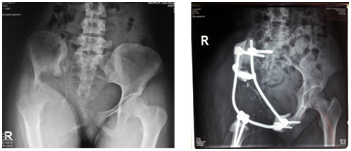

The surgery lasted for 12hours with 4000ml blood loss. We performed wide marginal excision Post-operative X ray showed interconnecting pedicle and rodsystem reconstructed the pelvicarch (Figure 2). The histopathological examination revealed a grade 2 chondrosarcoma with superior, medial, lateral and distal margin were tumor-free.

Figure 2 Pelvic AP plain radiograph. a. Pre-operative; b. Post-operative.

Post-operative range of motion was 0-45degrees hip flexion and patient could walk with crutches. Limb length discrepancy was 1cm. There was drop foot suggesting sciatic nerve palsy post-operatively. Patient was treated by medical rehabilitation department for regaining muscle strength and mobilization using ankle-foot orthosis. No other complications such as dislocation, deepvein thrombosis, emboli, infection, implant failure, local recurrence or distant metastases were observed in 6 months and 1 year follow up. The MSTS score was 16 and 21 in 6 months and 1 year follow up suggesting an improving functional outcome (Table 1).